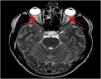

En la resonancia magnética cerebral con contraste se describe una discreta hiperseñal de ambos nervios ópticos más marcada en secuencia T2 (fig. 1) con marcado realce de las lesiones tras la inyección de contraste intravenoso en secuencia 3DT1 (fig. 2). Estos hallazgos son sugestivos de neuritis óptica bilateral. En el resto del estudio por neuroimagen no se objetivaron otras alteraciones (cerebro y médula espinal).